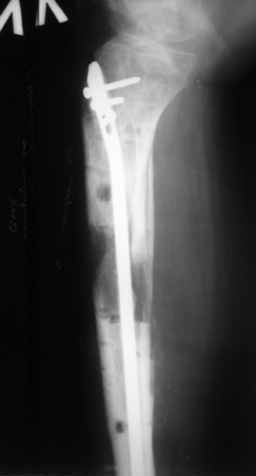

Ерсин, мы тоже имеем опыт такой фиксации. Подобную операцию за последние 3 года мы сделали трем пациентам. Снимки одного из них я прилагаю.

К сожалению, ни в одном из этих 3-х случаев мы не получили удовлетворяющего нас результата. Очень трудно провести штифт, введенный антеградно ровно по центру таранной кости. Отсутствие подвижности между диафизом и дистальным отломком большеберцовой кости (после фиксации в аппарате в течение 1-2 мес) очень усложняет проведение штифта в центр блока таранной кости. Поэтому мы от этого пока отказались, и проводим штифт через пятку. При данном варианте фиксации подобных проблем не возникало ни разу.

Больному выполнена резекция малоберцовой кости, ВХО раны, сближение отломков. Резекция м\б через отдельный разрез. После ВХО компрессия в аппарате, края раны сближены наводящими швами (без натяжения).

В случае гладкого заживления раны, при условии положительного решения вопроса с металлом, планируем перемонтаж аппарата Илизарова, дополнительную резекцию дистального отломка, выведение полокости голеностопного сустава в правильное положение (см. боковую Р-грамму), одномоментно остеотомия большеберцовой кости. После восстановления длинны голени, по всей видимости, артродез голеностопного сустава.

Рентгенограммы прилагаются. Фото местного статуса выложу в ближайшее время.